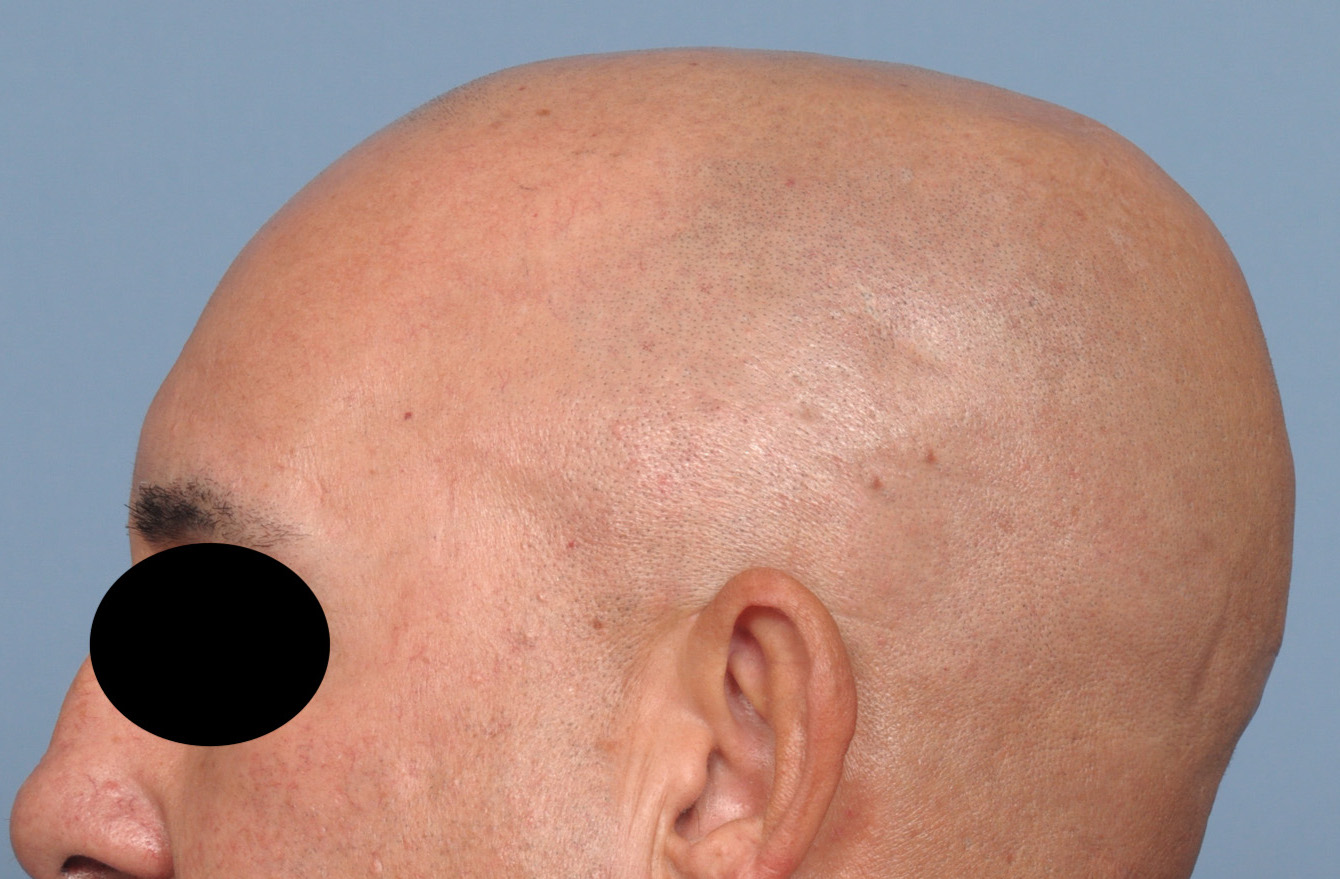

Patient 28

Desire for rounder shape to the top of the head from a congenital parasagittal deficiency skull shape.

Custom skull implant designed to fill in the parasagittal deficiencies.

Desire for rounder shape to the top of the head from a congenital parasagittal deficiency skull shape.

Custom skull implant designed to fill in the parasagittal deficiencies.